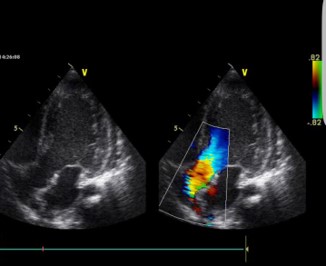

At 2 years of age, a gallop rhythm was detected on cardiac auscultation, raising concerns about underlying cardiomyopathy (CM). Echocardiography revealed hypertrophic cardiomyopathy (HCM) with diastolic dysfunction and mitral valve regurgitation (E/E’ 12.5, LVEDD 32 mm, z-score +1,24; LVESD 15 mm, z-score 1,20, IVS 6 mm, z-score +1,30, LVPW 6 mm, z-score +2,26, LVFS 53%, LVEDV 56 ml/m2, LVESV 26 ml/m2, LVEF 54%) (Figures 1a & 1b).

Figure 1a: Hypertrophic left ventricle and the mitral valve regurgitation.